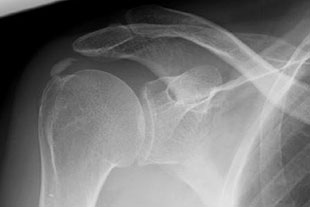

Röntgenbild Kalk

Im Röntgenbild und in der Sonographie des Schultergelenkes finden sich Kalkeinlagerungen, zumeist in der Supraspinatussehne (Teil der Rotatorenmanschette) von unterschiedlicher Beschaffenheit und in verschiedenem Ausbreitungsgrad.